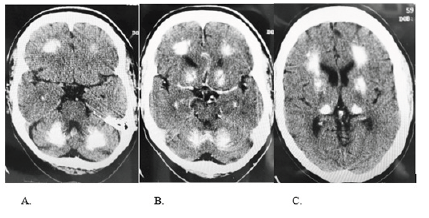

A 66 years-old-man presented with progressive word-finding difficulties and impulsive behavior. Examination showed nonfluent aphasia, anomia, impulse control disorder, executive dysfunction and ataxia. Neuropsychological testing was consistent with primary progressive aphasia. Labs were unremarkable, including parathyroid hormone, calcium, and phosphorus. CT head showed symmetric calcifications in basal ganglia, thalamus and cerebellum (Figure 1 A, B, C). Brain PET was normal. Fahr’s disease also known as an idiopathic basal ganglia calcification may have genetic, infectious, metabolic etiology and typically presents with movement disorders. Dysarthria is common, but aphasia has not been reported. 1,2 This unusual clinical presentation is likely secondary to the involvement of frontal projections [1,2].